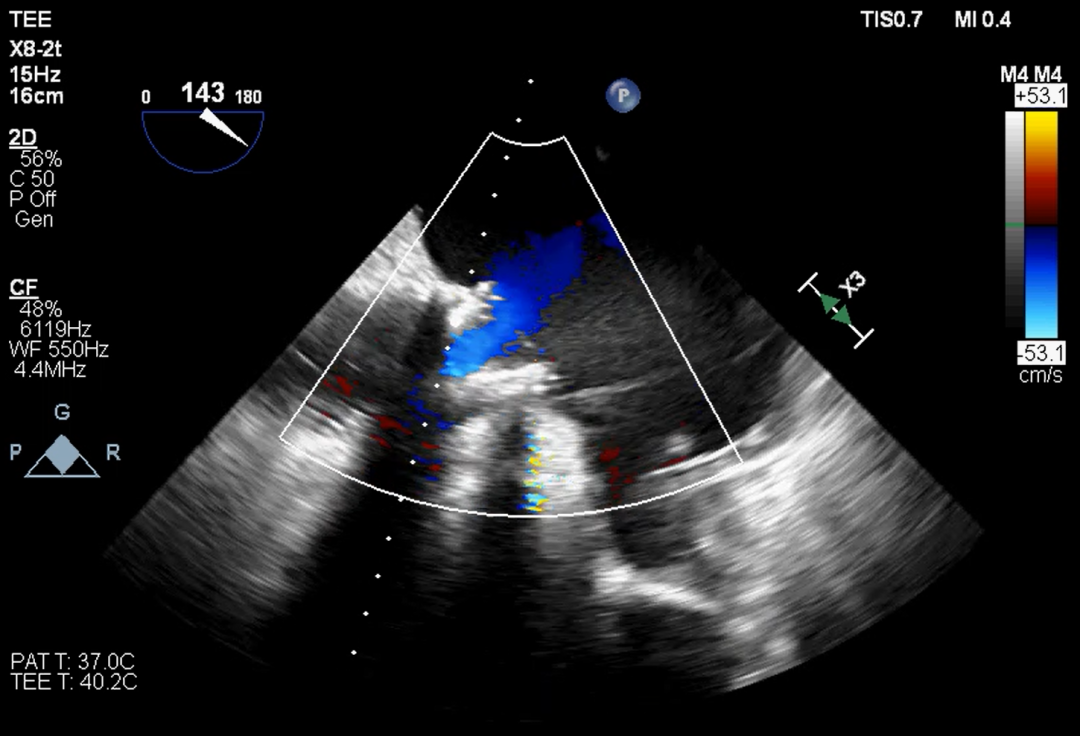

超声提示

影像分析

本例患者15年前因三尖瓣增厚伴重度反流,接受31#三尖瓣生物瓣置换。该类型的外科生物瓣在影像下透视性差,术中难以清晰捕捉其形态和位置。同时,其右心室狭小,留给介入瓣操作的空间有限,使得本次手术难度升级。宁波市第一医院心外科励峰主任团队凭借丰富的瓣膜外科手术经验,成功经右房途径TTViV植入一枚29#的J-Valve瓣膜。J-Valve经心尖介入瓣膜系统,在治疗生物瓣衰败的改为患者中行瓣中瓣植入术可以取得良好的临床效果。其独特的定位件设计,能够准确牢固地锚定在原生物瓣的瓣脚上,降低瓣膜移位的发生率。术后,患者三尖瓣跨瓣压差、反流及右房压均明显改善,即刻获益。